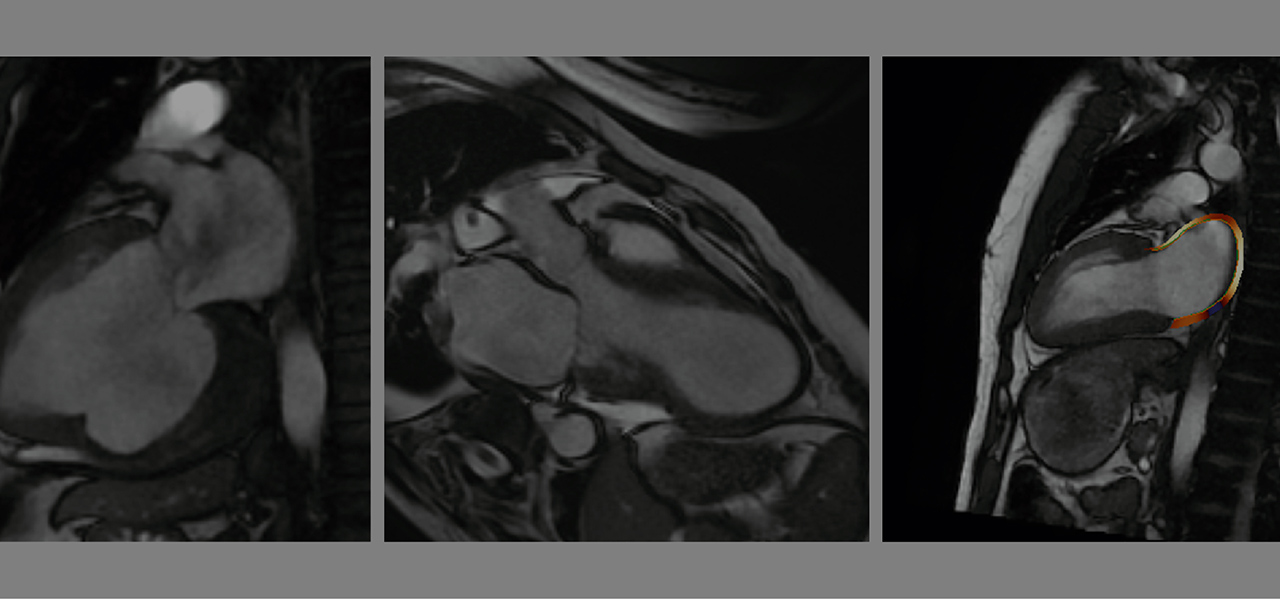

En este curso se trata de presentar desde los conceptos más básicos hasta los más avanzados en cardiorresonancia magnética (Cardio-RM) para que el especialista de imagen cardíaca adquiera los conocimientos más relevantes y más actualizados en esta técnica de imagen. Partiremos de los conocimientos de física básica y organizativos de las unidades de Cardio-RM, para posteriormente, valorar en profundidad cada una de las diferentes patologías cardiovasculares, y finalizar con los temas de mayor actualidad. Todos los temas irán acompañados de casos clínicos basados en casos reales que servirán para poner en práctica los conocimientos adquiridos en las lecciones teóricas. Consideramos que los conocimientos teórico-prácticos de este máster servirán de base para los futuros especialistas dedicados a Cardio-RM y de actualización para los especialistas en los que la Cardio-RM ya forma parte de su actividad clínica habitual.

Parte teórica: En esta parte se desarrollan los conocimientos y bases científicas de cada tema siguiendo la medicina basada en la evidencia. Se estructura en forma de un manuscrito tipo revisión con gráficos, tablas, figuras y videos de apoyo.

• Casos clínicos estructurados, comentados y resueltos por el profesor. La descripción de los casos se acompañará de imágenes y videos accesibles.